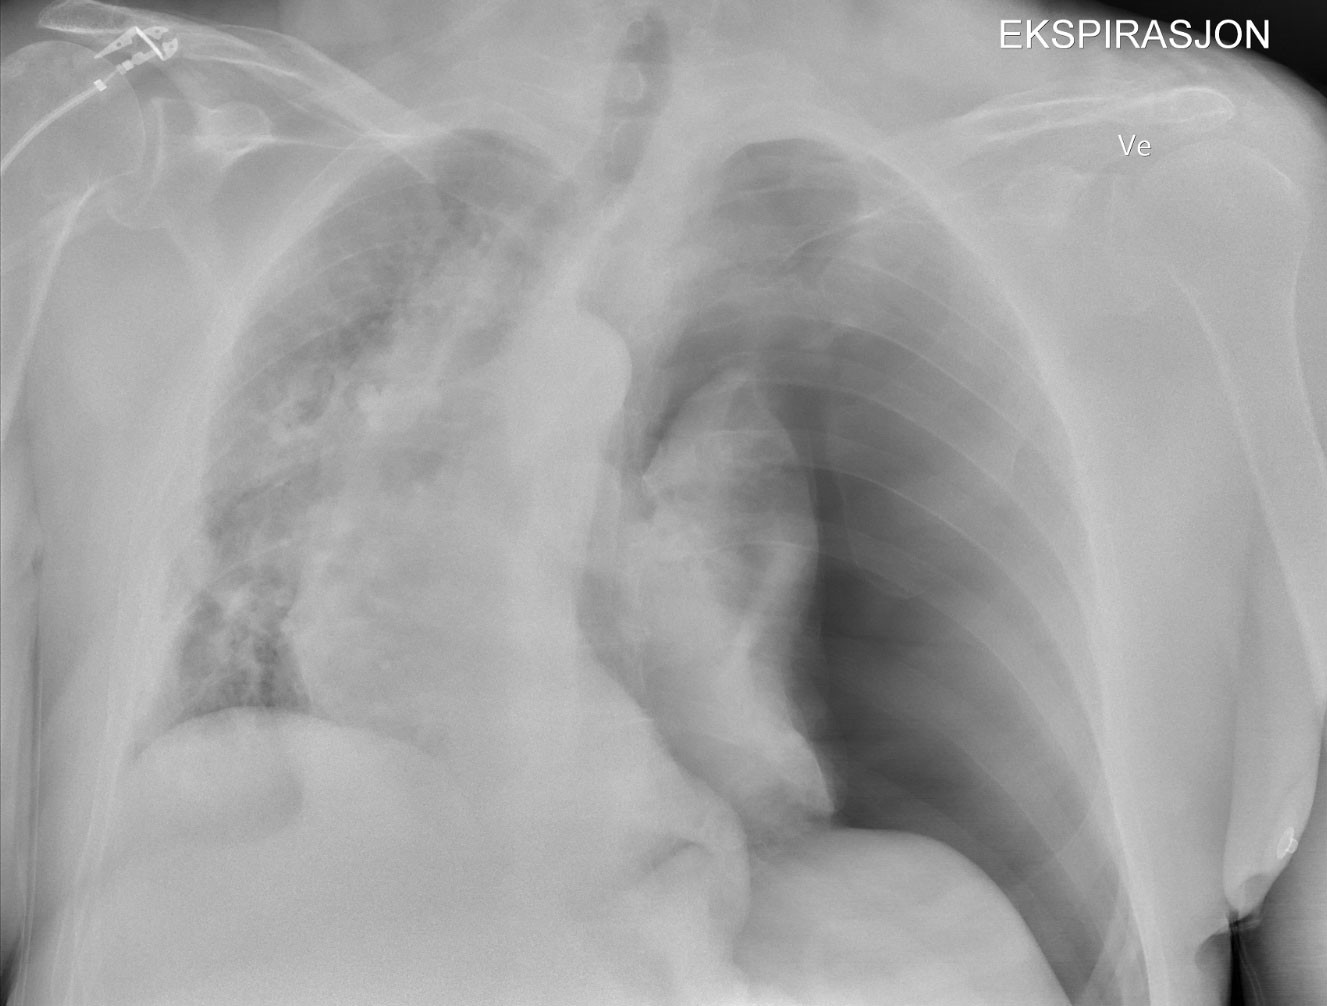

One hour before the end of the operation, oxygen saturation dropped to 89 %, tidal volume from 550 ml to 366 ml, and mean blood pressure from 70 mmHg to 60 mmHg. Oxygen in inspired air was increased from 40 % to 100 %, and inspiratory pressure was increased from 9 cm to 18 cm of water. Oxygen saturation rose to 91 % and blood pressure remained unchanged. No lung auscultation or blood gas analysis were performed. Surgery was completed, anaesthesia was stopped and the laryngeal mask was removed without difficulty. Upon arrival at the postoperative ward, oxygen saturation was 88 % despite the application of a non-rebreather oxygen mask. The patient was dyspnoeic, clammy and pale, with blood pressure of 90/60 mmHg. The duty anaesthetist was immediately called. In an ultrasound scan a few minutes later, the anaesthetist found an absence of lung sliding of the left pleural blades. Chest x-ray confirmed left-sided tension pneumothorax (Figure 1).